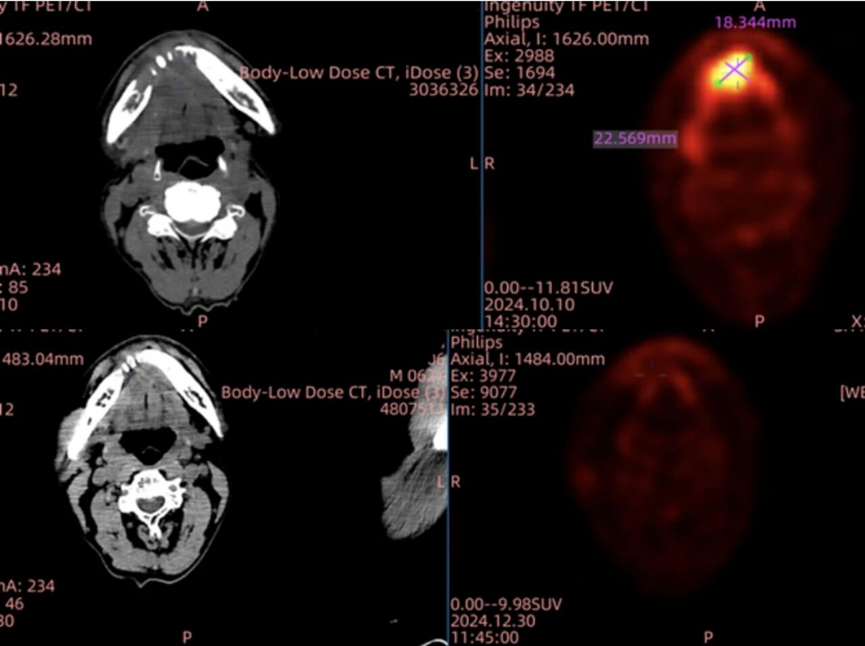

头颈鳞癌方面,GT201 同样交出惊艳答卷,其在晚期头颈部鳞癌的小样本亚组中,实现了 100% 的疾病控制率。上海交通大学医学院附属第九人民医院何悦教授团队开展的临床研究显示,一名口底癌伴下颌骨侵袭及颈部多发淋巴转移的患者,在 TIL 输注后仅 3 周病灶显著缩小达到临床部分缓解(PR),9 周随访时所有病灶完全消失,实现完全缓解。